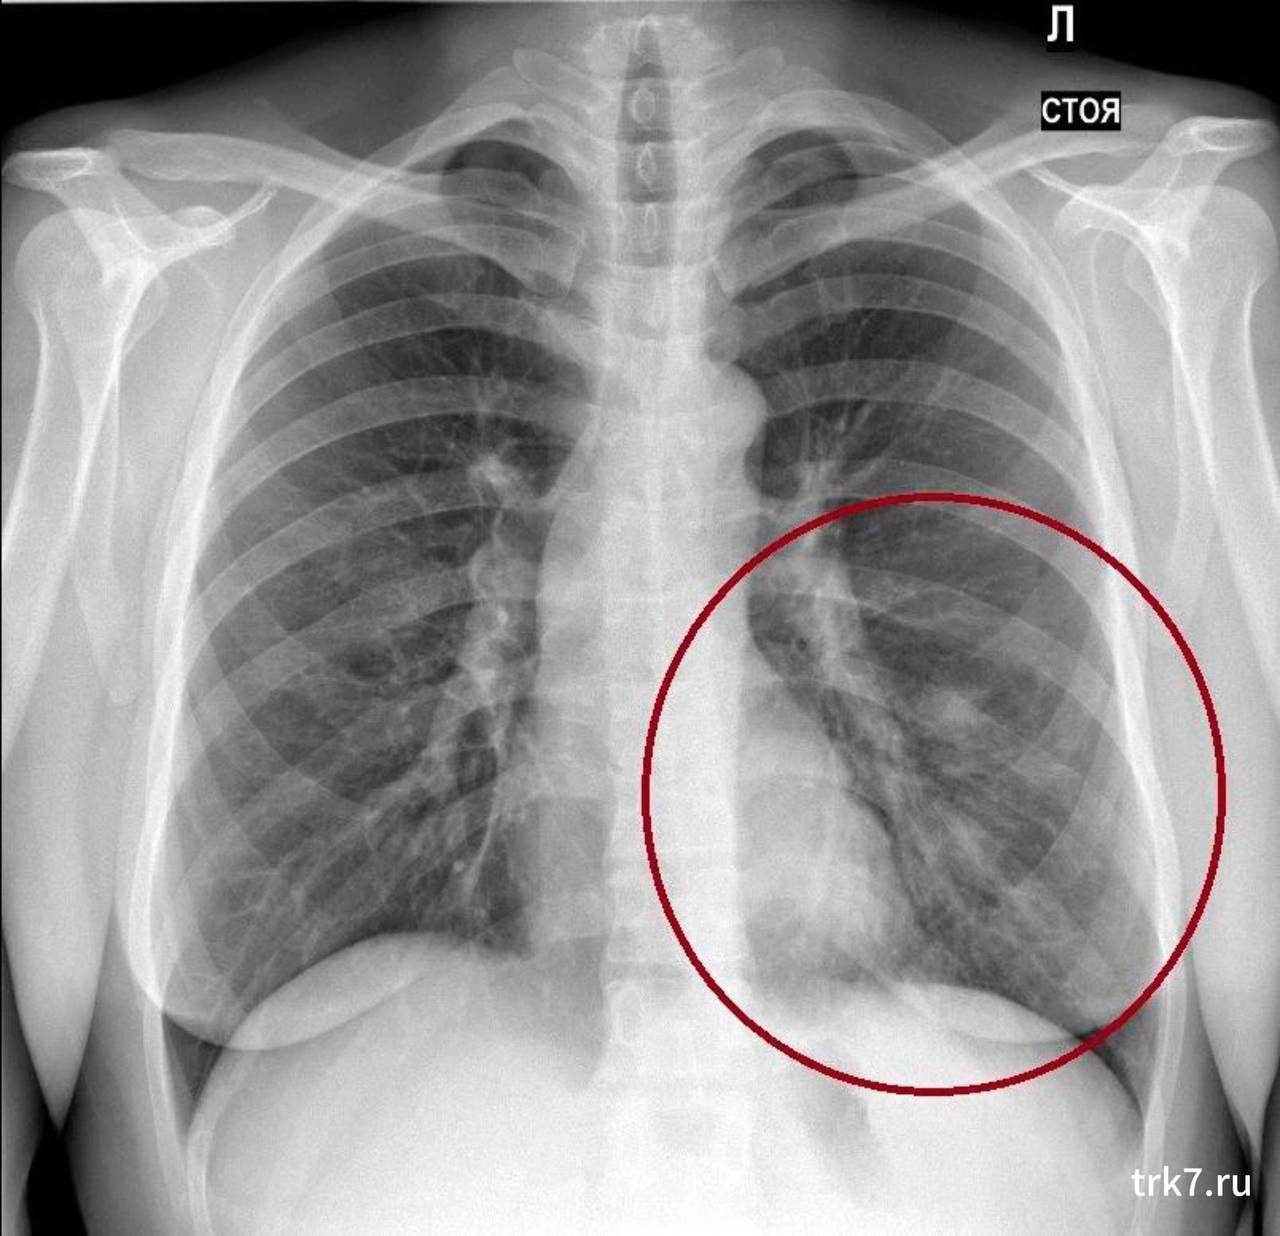

Фото Легких После Вейпа 107 фотографий